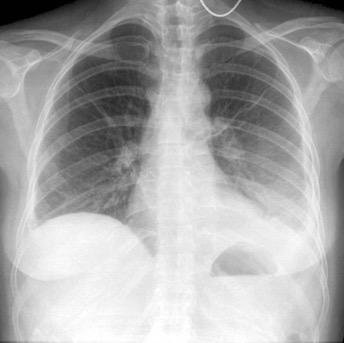

500 cc. Borramiento diafragmático

1000 cc

Los hallazgos radiológicos dependen de.

1. Cantidad de líquido

2. Su distribución. (dependiente de la posición)

3. Si es libre o está tabicado (formación de fibrina)

Líquido libre Líquido “subpulmonar”